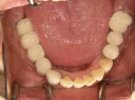

47歳女性

ブリッジや義歯でも可能な症例ですが、残っている歯を守りたいという患者さんの希望によりインプラント施術。

なお、この患者さんは歯医者の方で、専門知識の高い歯科医師の方にも喜んでもらえて大変光栄でした

術前

術後